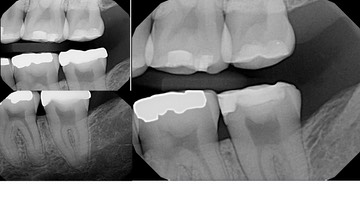

Kris NIp #18 bitewing radiograph